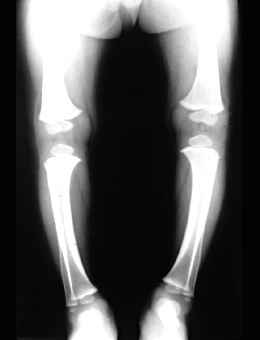

Otro de los trastornos que provocan el reblandecimiento y debilitamiento de los huesos en los niños, es el raquitismo, causado principalmente por falta de vitamia D. Esto puede conducir a una deformación esquelética como, por ejemplo, una curvatura de la columna vertebral o de las piernas.

La vitamina D regula la absorción del calcio en el cuerpo y controla los niveles de calcio y fosfato en los huesos. Proviene de los alimentos y también es producida por la piel durante la exposición a la luz solar

El raquitismo se produce durante la época de crecimiento de los huesos. Esto puede ocurrir:

- Cuando el suministro de vitamina D en la dieta y la exposición al sol son inadecuadas

- Al metabolismo anormal de la vitamina D

- A que los tejidos son resistentes a la acción de la vitamina D.